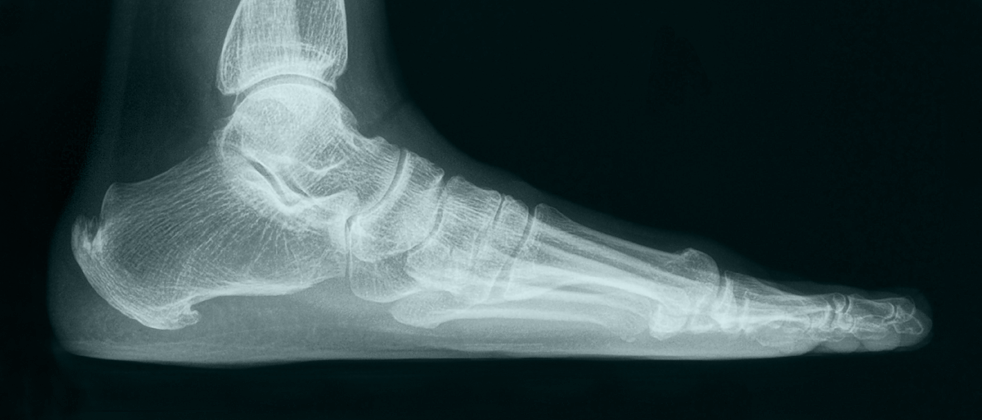

Η ποδική καμάρα βρίσκεται στο έσω χείλος του ποδιού και δημιουργείται από τη πτέρνα, τον αστράγαλο, το σκαφοειδές οστούν, τα σφηνοειδή οστά καθώς και τα τρία πρώτα μετατάρσια. Η ιδιαίτερη αυτή κατασκευή υποστηρίζεται από τους συνδέσμους και τους μύες προσδίδοντας στο πόδι την απαραίτητη ελαστικότητα διευκολύνοντας τη βάδιση, το τρέξιμο και την αλτική ικανότητα του ανθρώπου.